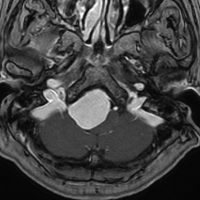

大後頭孔(大孔)髄膜腫 foramen magnum meningioma)

この腫瘍はfarlateral approachなどの頭蓋底手術をしなくても,外側後頭窩開頭で全摘出できます。要領は,S状静脈洞の下端の周囲骨を削除することです。大後頭孔髄膜種は延髄を圧迫するので巨大なものはありません。出血のコントロールや延髄からの剥離は比較的容易なものが多いでしょう。舌咽神経と迷走神経損傷を避けることが重点となります。

迷走神経と舌咽神経は機能温存できました。舌下神経が腫瘍の表面に薄く広がり剥がすことができずに半分以上を切断しています。でも片側舌下神経麻痺では日常生活に困ることはあまりありません。